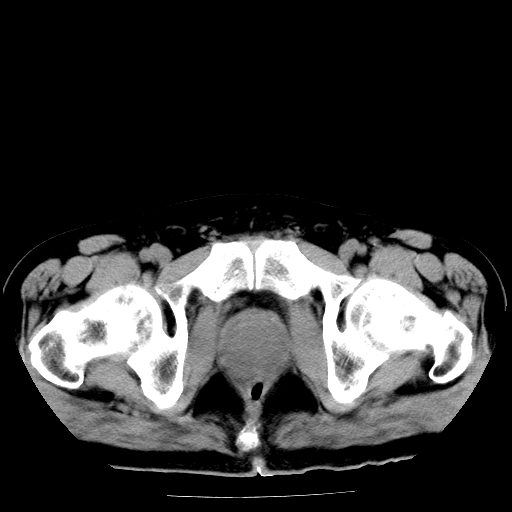

男,66岁,直肠癌术后一个月,化疗前ct检查。

膀胱充盈不太好,前列腺较大,前列腺肥大?占位?建议:结合临床.

直肠癌造瘘术后改变,直肠周围软组织增厚,盆腔多发淋巴结转移。前列腺肥大。

前列腺肥大。

盆腔内有很多点点,可能是淋巴结转移,建议增强。“直肠周围浸润”无法与术后斑痕鉴别,治疗后再说